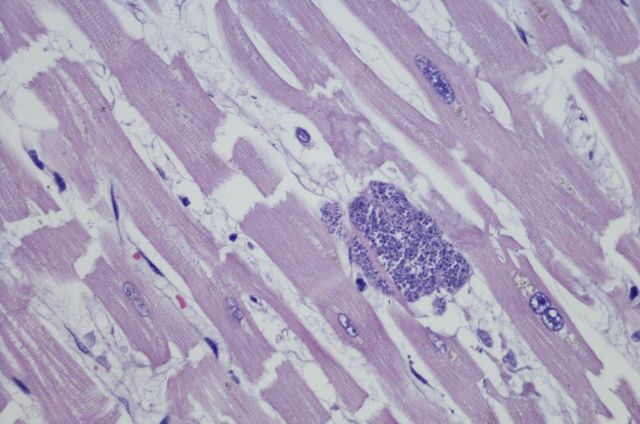

弓形虫病是由弓形虫(Toxoplasma gondii)寄生在细胞内引起的流感样疾病。

弓形虫病经常引起流感样症状,通常情况下无需治疗即可消退。然而,一些人可能会出现更严重的并发症,寄生于细胞内的弓形虫,随血液流动,到达全身各部位,破坏大脑、心脏、眼底,使人的免疫力下降,从而罹患各种疾病。